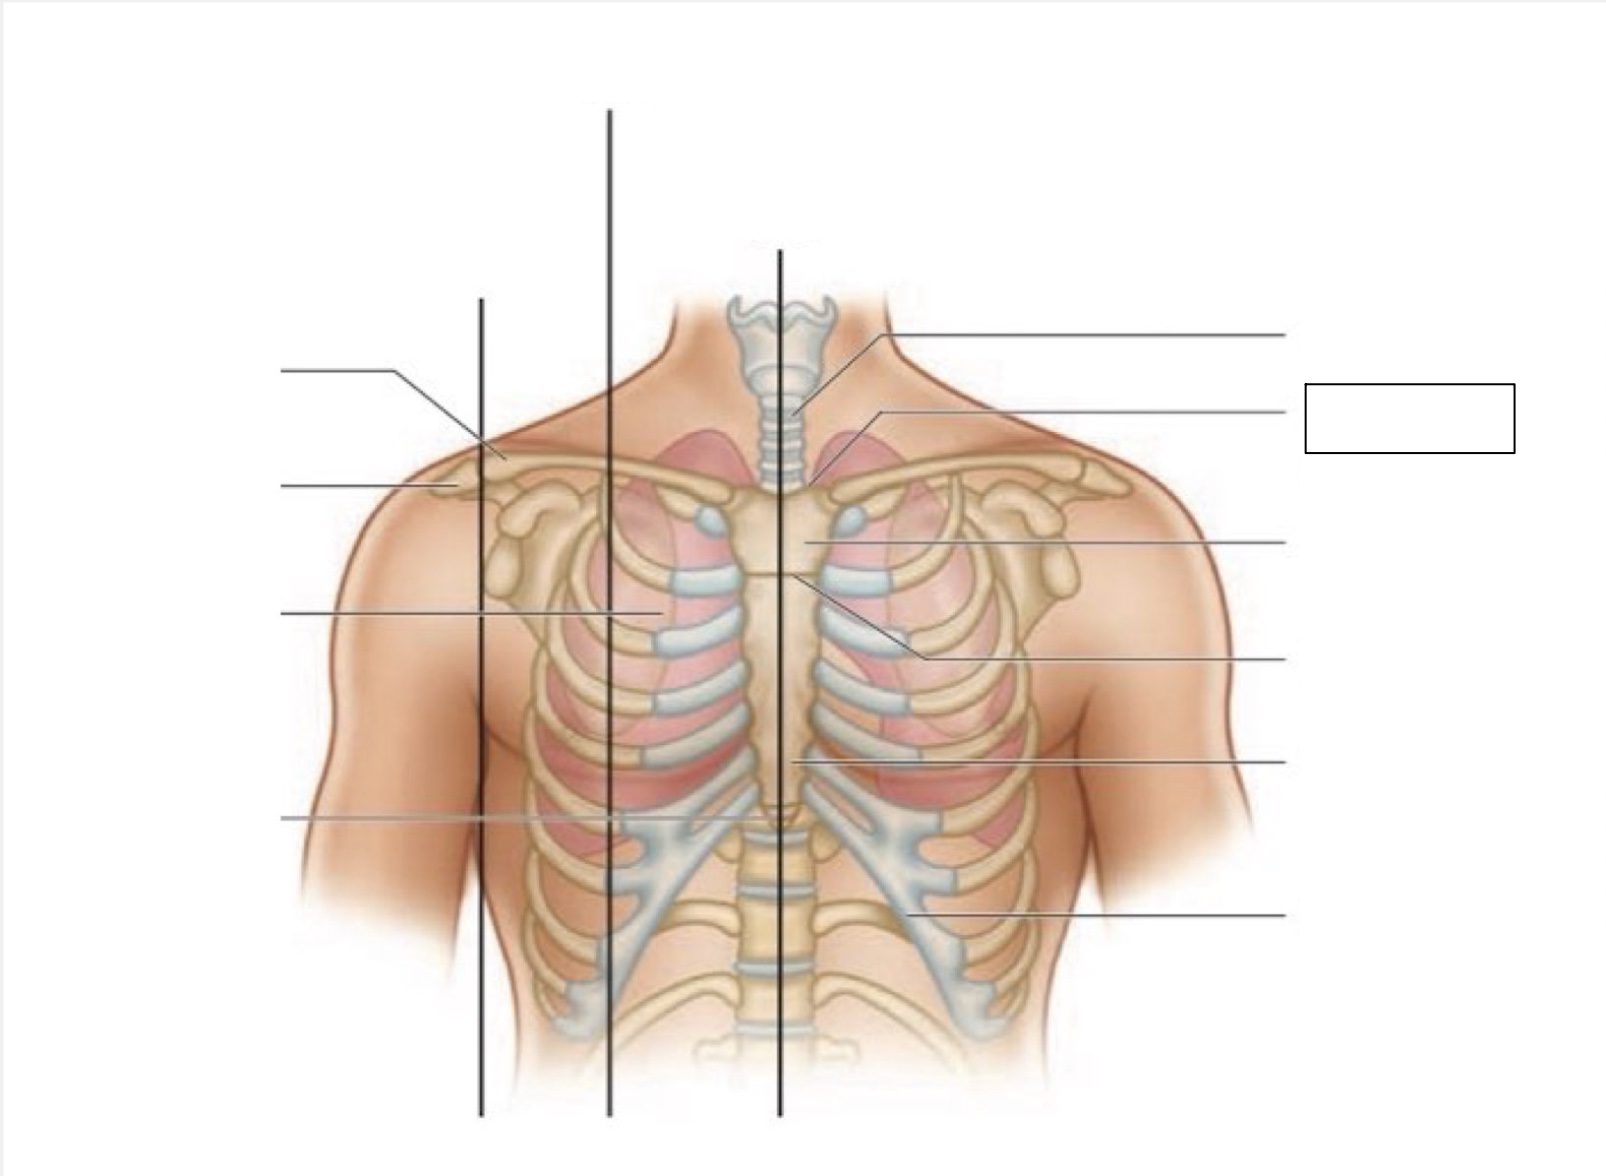

midsternal line

trachea

suprasternal notch

manubrium

angle of Louis

sternum

costal margin

xiphoid process

intercostal space

acromion

clavicle

anterior axillary line

midclavicular line

inferior angle of scapula

scapula

midscapular line

midspinal line

spinous process